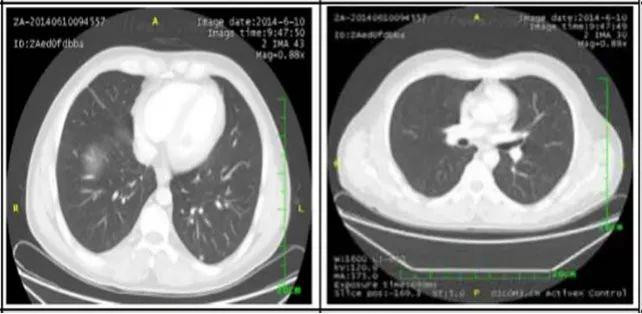

2. 肺部病灶治疗前后核磁对比:

肺部转移病灶在用药后2个月明显缩小,4个月后病灶基本消失。

治疗16个月